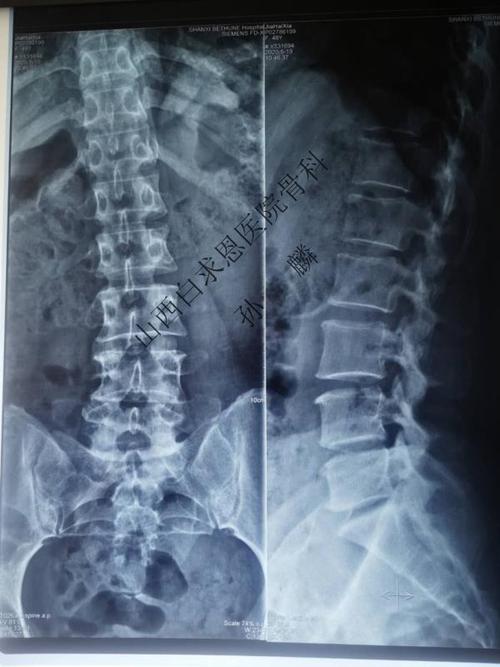

正常腰椎x片

正常腰椎x片,正常腰椎x光片图

我院腰椎正侧位及动力位x片显示,患者腰椎呈姿势性侧弯,退变明显,l4/5